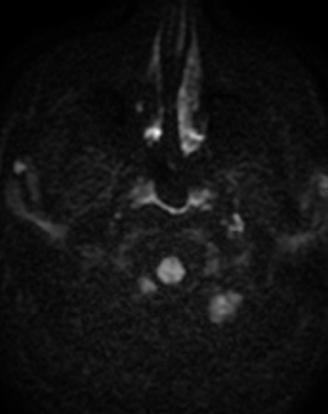

b. Ponderația DWI (Diffusion Weighted Imaging)

DWI este o secvență funcțională extrem de bună în analiza măduvei osoase datorită sensibilității sale în evaluarea densității celulare, precum și a conținutului relativ de apă și grăsime [16]. Secvența DWI este achiziționată în plan axial folosind diferite valori b (0, 50, 200, 600, 800 s/mm2). Semnalul obținut va fi direct proporțional cu numărul de celule prezente pe mm2 precum și cu puterea gradientului de difuzie utilizat [17]

Evaluarea inițială a măduvei osoase se va face prin examinarea semnalului corpilor vertebrali pe imagini cu valori b ridicate (în general b=800); astfel, în cazul evidenței leziunilor în hipersemnal pe ponderația DWI, acestea vor fi încadrate ca zone de infiltrare tumorală dacă valorile ADC sunt invers proporționale; această metodă de evaluare inițială este extrem de utilă în practică întrucât leziunile patologice sunt extrem de evidente atât pentru radiolog cât și pentru clinician[18].

Patternuri de infiltrare a măduvei osoase în MM decelate prin IRM (figura )

Leziunile infiltrative și nodulare întâlnite în MM prezintă hiposemnal T1 datorită absenței grăsimii și cantității crescute de plasmocite din interior; ele prezintă în general un semnal T1 scăzut în comparație cu discurile intervertebrale și musculatura. Pe de altă parte, leziunile prezintă aspect hiperintens pe secvențele T2 FAT SATURATION sau STIR datorită conținutului ridicat de apă și celule, aspect similar altor leziuni osoase maligne[19].

Leziunile MM sunt prezente predominant în scheletul axial și anume vertebre (66%), pelvisul osos (30%) și într-o măsură mai mică la nivelul scheletului extra-axial (coaste, schelet apendicular) [20] În literatură sunt descrise cinci tipuri de infiltrare a măduvei osoase în mielomul multiplu: măduvă cu aspect normal, infiltrare focală a măduvei osoase, infiltrare difuză, infiltrare de tip “sare și piper” și infiltrare combinată focală și difuză [21, 22]; Există o multitudine de studii apărute în literatură care corelează aceste tipuri de infiltrare medulară cu modificările vizualizate la examenele morfo-patologice [23, 24]. În majoritatea cazurilor de MM (28%) se observă un aspect normal al măduvei osoase, cu hipersemnal T1 omogen al acesteia; în cazul infiltrarii, focale se observă diverse leziuni focale T1 hipointense, care pot apărea oriunde la nivelul scheletului; în cazul infiltrării difuze, se observă hiposemnal T1 difuz la nivelul intregii măduve osoase, uneori în caz de infiltrare severă, semnalul fiind chiar mai redus decât cel al discului intervertebral. În doar 3% din cazuri se observă un model de tip „sare și piper” și în 11% din cazuri se poate observa un model mixt de infiltrare nodulară și difuză [22, 25]

Tipuri de afectare medulară în mielomul multiplu: aspect normal imagistic(a), infiltrare focală(b), infiltrare difuză(c) infiltrare de tip ‘sare și piper’, infiltrare mixtă de tip focal și difuz(d). Departamentul de Radiologie al Spitalului Clinic Municipal de Urgență - Timișoara/RO